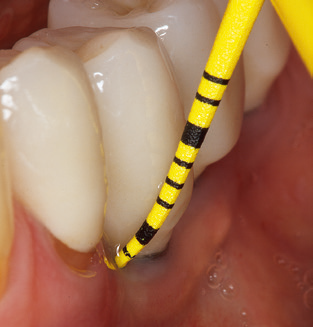

Of course, working tips for the cleaning of implant surfaces are also indispensable for SPT in patients fitted with implants. The implant cleaning attachment on the system used here is characterised by its tapered, hexagonal design. This design allows light, atraumatic penetration of the peri-implant pocket and displays a good cleaning performance (Fig. 7).

Fig. 4: Flexible probes with millimetre markings are recommended for the probing of dental implants (e.g. Colorvue Kit PCV11KIT6, Hu­Friedy). – Fig. 5a and b: A straight working tip (1P, W&H Dentalwerk Bürmoos GmbH) is a suitable instrument for use on all natural teeth. – Fig. 6: Curved working tips (3Pr/3Pl, W&H Dentalwerk Bürmoos GmbH) lend themselves to the processing of difficult-to-reach areas of the tooth and root surfaces (e.g. furcations). – Fig. 7: The tapered, hexagonal implant cleaning tip (1I, W&H Dentalwerk Bürmoos GmbH) permits atraumatic and efficient cleaning of the crown and abutment surfaces. – Fig. 8: Titanium and carbon curettes are suitable instruments for the manual cleaning of the implant surfaces.